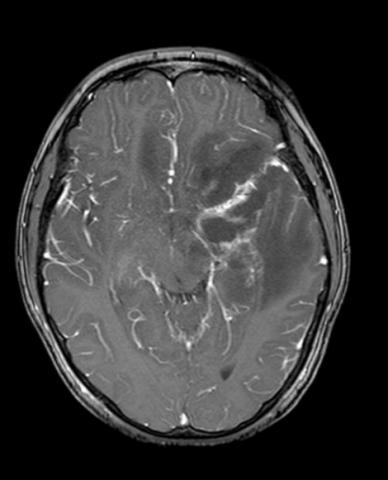

Evacuation of intracerebral hematomas by Neuroendoscopy: results in a series of cases

JERSON FLORES C.